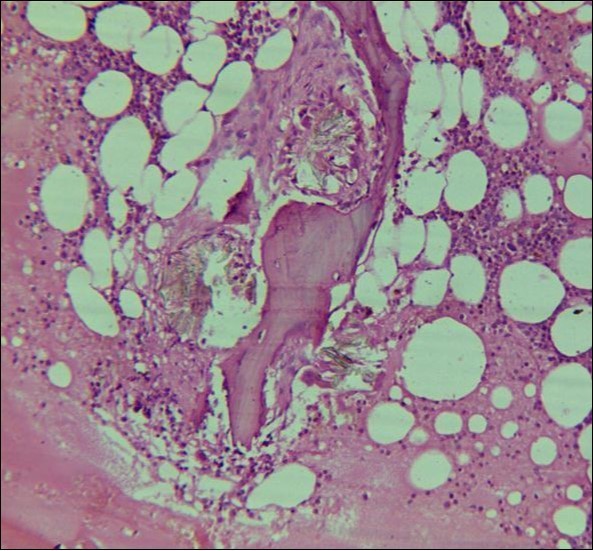

A 24 years old male, presented with the complaints of multiple recurrent renal stones bilaterally. He was on dialysis since last 6 months. His brother had died with chronic renal insufficiency secondary to nephrolithiasis. His routine investigations at the time bone marrow studies revealed anemia with a Haemoglobin of 6.6g/dl, White blood cell count of 5.3 x 109/l; Platelet count of 228 x 109/l. Serum Creatinine was very high 13.9mg/dl. X Ray Abdomen revealed multiple bilateral renal calculi and in addition gall bladder calculi. On ultrasound abdomen his right kidney was 10.5cm x 5.6 cm, had a cyst in the upper pole, multiple calculi were causing hydronephrosis. Left kidney was 8.5cm x 4.8 cm, with multiple calculi. Both kidneys showed increased echogenecity. Serum oxalate levels were 91.2 mg/dl (Normal Range 1-2.4 mg/dl). His Parathyroid MIBI scan was normal, but plasma Parathyroid hormone levels were 373 pg/ml (Normal Range 16 – 87pg/ml). Normochromic normocytic anaemia was present, with normal WBC and platelet count. The bone marrow aspirate was unsuccessful. The trephine biopsy revealed reduced cellularity, depressed erythropoeisis with partly replaced haemopoietic tissue with calcium oxalate crystals (Figure 4) which showed birefringence on polarized light (Figure 5).

Figure 4.Photomicrograph of bone marrow core from case2 showing Para trabecular arrangement of calcium oxalate crystals. Increased fat spaces and depressed erythropoiesis is evident.

Figure 5.Calcium oxalate crystals showing birefringence under polarized light.

Systemic oxalosis can be a primary or a secondary disease. Primary hyperoxaluria Type 1 (PH 1) is due to the deficiency of glyoxylate aminotransferase and Type II due to that of glyoxylate reductase/D-glycerate dehydrogenase. PH 1 is an autosomal recessive disorder characterized by hyperoxaluria, calcium oxalate urinary lithiasis in childhood, nephrocalcinosis and renal failure which in turn leads to high blood oxalate levels and precipitation occurs throughout the body in the skin, blood vessels and joints. Secondary oxalosis occurs due to oxalate-rich diet, increased absorption or production of oxalate and reduced excretion as seen in renal failure. Variable degree of cytopenias or pancytopenia may accompany extensive oxalosis. Bone marrow aspirate may be unsuccessful due to extensive crystal deposition or accompanying fibrosis. Calcium oxalate crystals are well demonstrated on trephine biopsy with associated fibrosis and occasionally granulomas. They have a grey-yellow radial arrangement on hematoxylin and eosin staining and are birefringent under polarized light.4 Liver biopsy is the confirmatory test which demonstrate reduced glyoxylate aminotransferase activity (PH1). Molecular diagnosis, being non-invasive, is preferred, if available.5 An early diagnosis of oxalosis is of immense value, because at a stage when renal failure has not set in, proper management can arrest or at least delay the progress of disease. However, in patients who have already developed renal failure at the time of diagnosis, a combined liver and kidney transplantation offers the only salvation.6